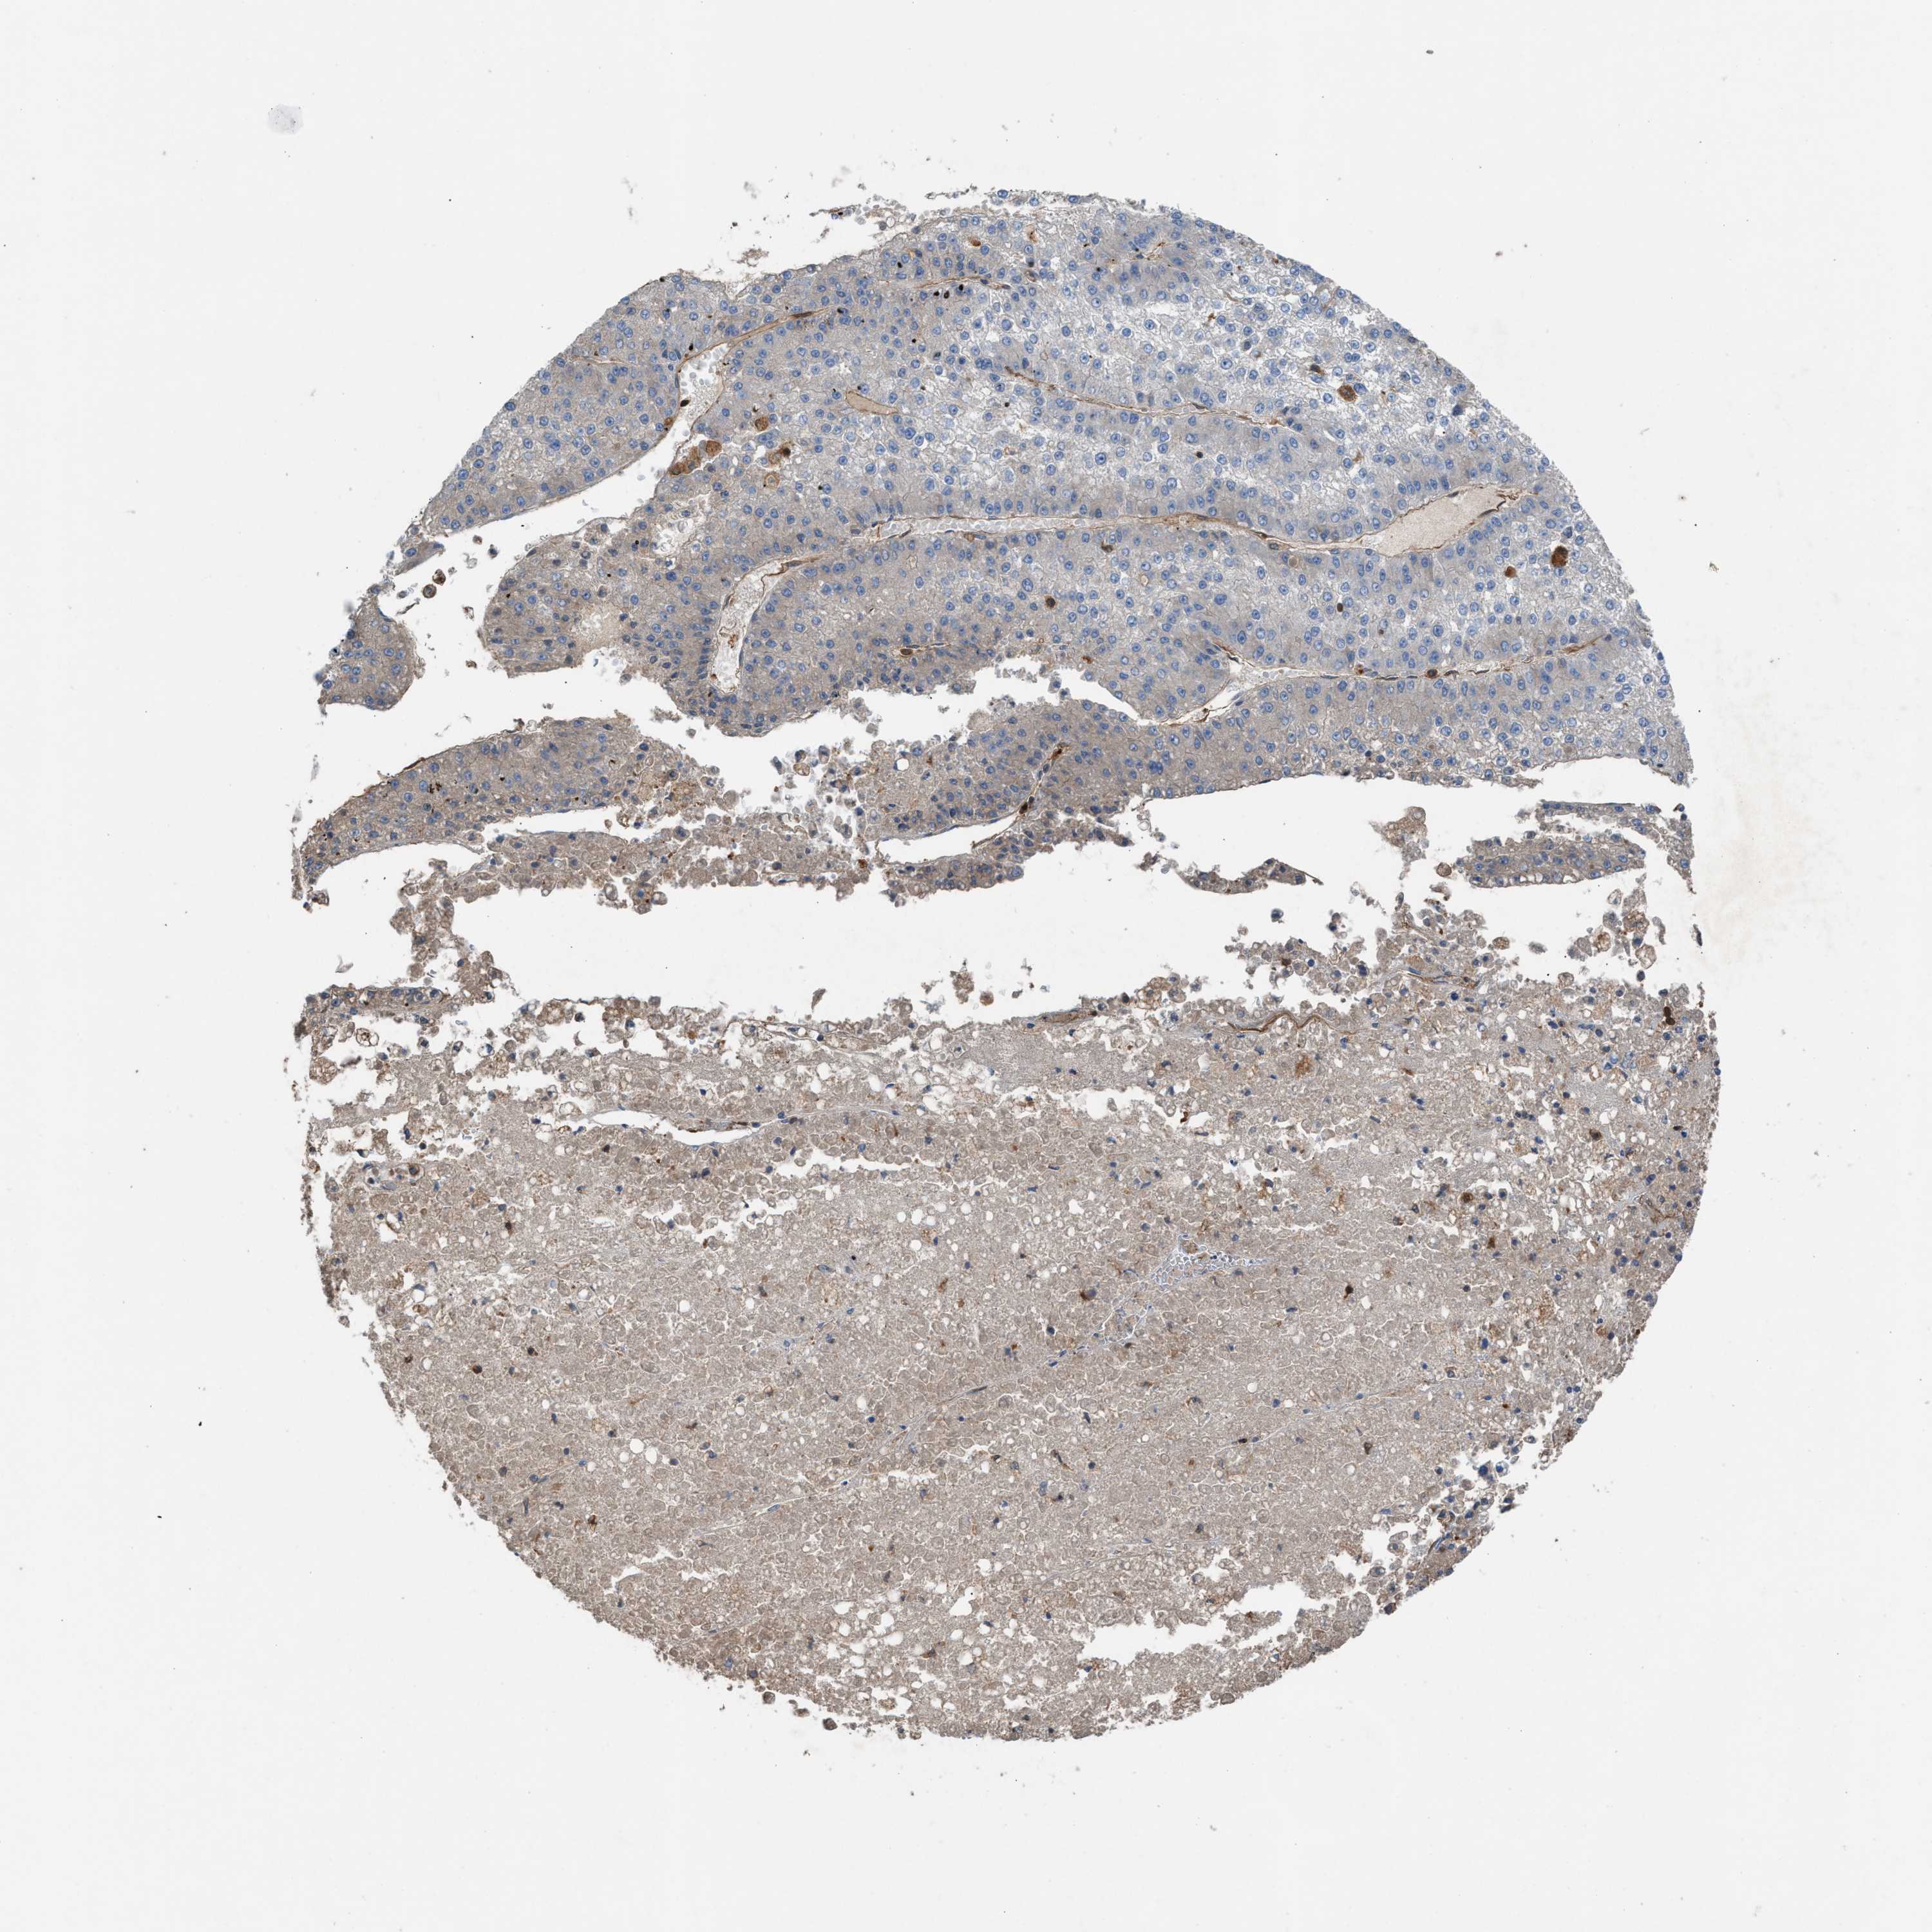

LIVER CANCER - Protein expressioni

A mouse-over function shows sample information and annotation data. Click on an image to view it in a full screen mode. Samples can be filtered based on level of antibody staining by selecting one or several of the following categories: high, medium, low and not detected. The assay and annotation is described here.

Antibody stainingi

Antibody staining in the annotated cell types in the current human tissue is reported as not detected, low, medium, or high, based on conventional immunohistochemistry profiling in selected tissues. This score is based on the combination of the staining intensity and fraction of stained cells.

Each image is clickable and will lead to virtual microscopy that enables deeper exploration of all samples and also displays staining intensity scores, fraction scores and subcellular localization as well as patient and tissue information for each sample.

Antibody HPA021545

Antibody HPA021849

Staining

High

Medium

Low

Not detected

Intensity

Strong

Moderate

Weak

Negative

Quantity

>75%

75%-25%

<25%

None

Location

Nuclear

Cytoplasmic/membranous

Cytoplasmic/membranous,nuclear

Cholangiocarcinoma

Carcinoma, Hepatocellular, NOS